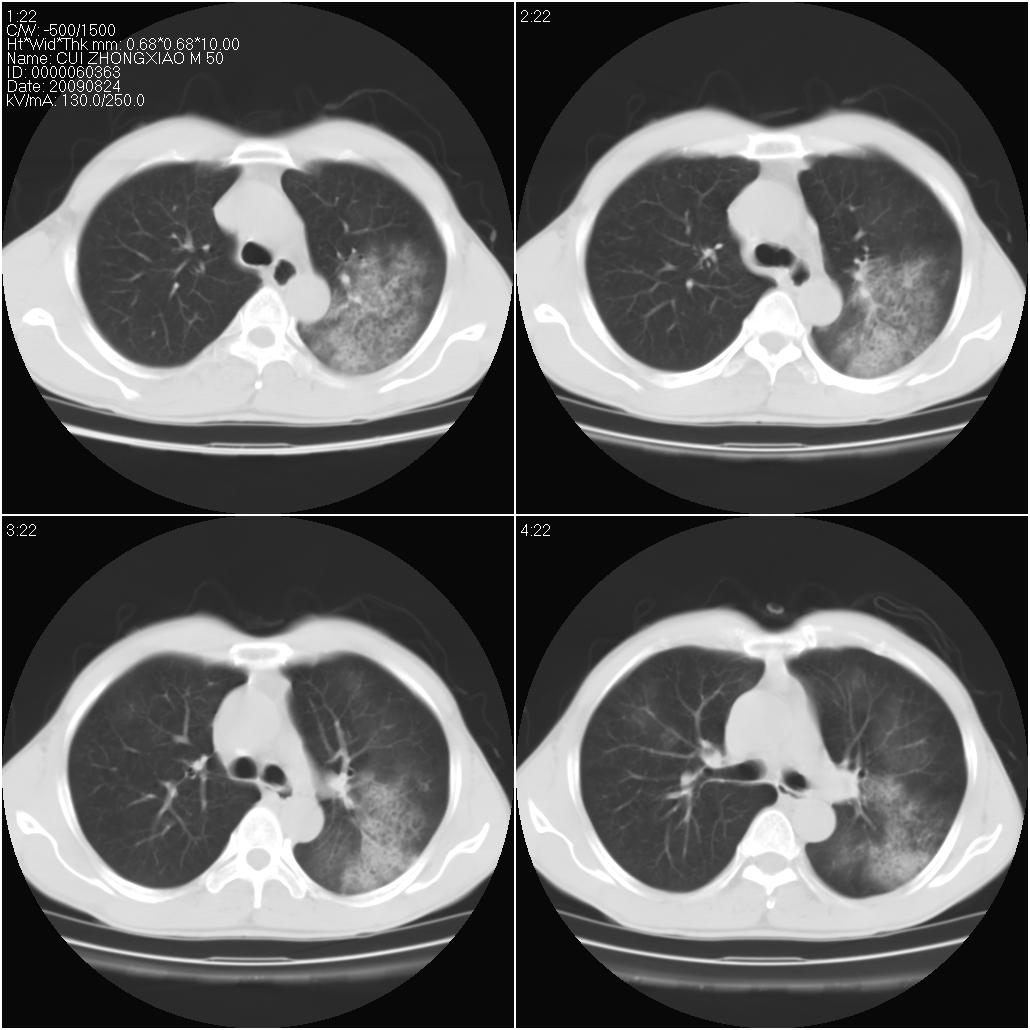

标题: CT21851:男性,50岁。间断性咳嗽半年。 [打印本页]

标题: CT21851:男性,50岁。间断性咳嗽半年。

磨玻璃样改变(左肺及右肺上叶前段),边缘模糊,考虑炎症,建议严格抗炎治疗后复查除外肺泡蛋白沉积症或肺泡出血(病人有咯血吗) 肺泡癌.

双肺磨玻璃征改变。。。支持楼上

考虑以感染性病变,以结核可能性大,建议治疗后复查。